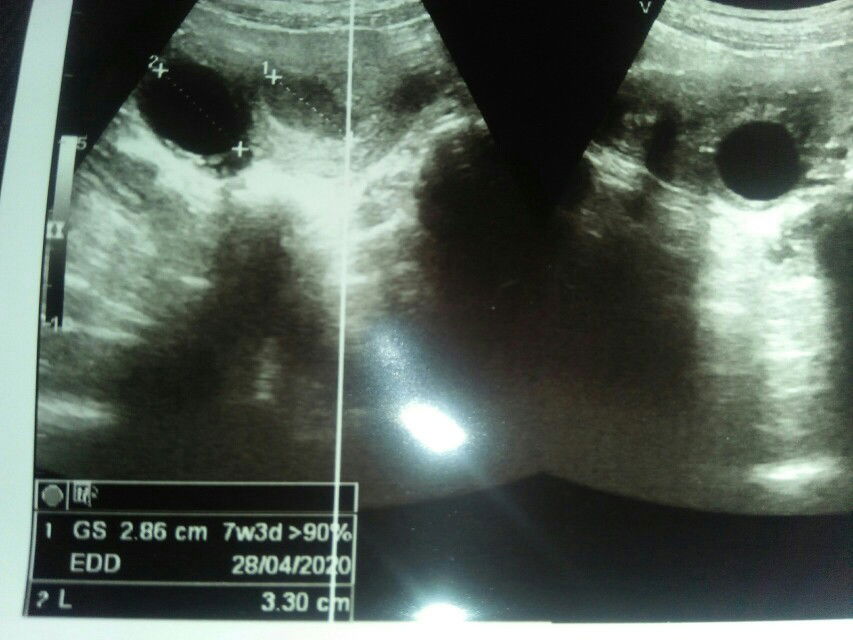

Seminggu yang lalu ku hamil usia kandunganku 6week dan terjadi flek sekitar 2 jari, aku cek usg ternyat janinx masih blum kelihtan masi tampak kanongnya saja dan ternyata ada kista dg ukuran 3.30 cm. Diberi obat penguat dan vitamin sama dokter dan dr menjlskan, jgn capek capek ya bu,, makannya yang teratur kurangi naik turun tangga kalo bisa hindari kndungn ibu masuk 6week tp masih kntong bkal janin blm tampak saya kasi obat penguat agar bisa bertaeung dengan si kista... Kalo semisal terjadibpendrhn hebat segera ke bidan terdekat. 1.2.3.4.5hari berlalu tanpa ada keluhan apapun hari ke 6 pukul 1 dini hari aku pendarahan seperti org mens. Kata suami sudh mie jgn gerak tdor ada makan disuapin pipis pun di bopong alhamdulillah darah mmpet keesokn harinya hari jumat memng sengaja g bangun bangun dari tmpat tidur karna tkod pendrhn dn alhasil si drah keluar lagi 5x gnti cd dn akhirnya saya gnti pakai pembalut. Saya dan suami siap siap ke dr spog. Habis mandi duduk duduk depan teras perut sakit sekali seperi diperas baru kali ini merasakan sakit yang sangat hebat dibawlah saya kebidan Kata si budan lngsng aja bawa ke dr spogx karna saya takot trjadi apapa karna ada kista... Langsung saya bergkatbke dr spog dan rasa nyerinya sudh hilang... Di usg yg kedua kalix... Kista masih ttap bakal janin tampak tapi smar dengan ukuran 1.27 uk 7w3d detak jantung tidak ada.. Dan plasenta sudh terkikis dan ternyata darahbyang keluar itu dari plasenta dedek bayi... Sedih rasanya ketika dr menyarankn di kuret krna meski diperthnkan janinx g bakaln sempurna karna plasenta sudah terkikis.... Alhasil pagibtadi saya di kuret dan disarankn jagn hamil dlu 3bulan untuk meliht pertmbuhn si kista dan si ddek kalah sama si kista Ya allah sedih rasanya kahamilan pertamaku harus verakhir dg seperti ini... Kehamiln yang sangat kami nantikan papa mama mertua sydh sangat senang mndegr kehamilnku ..tapi allah lebih sayang padnya... Adek maafin amie masih blm bisa jaga adek... Abie sma amie sayang sama adek makasih ya sayang sudah mau tinggal dirahim amie meski hanya 7 minggu ami sudh sangat bahagia... Amie sama abie akan selalu mendoakn adek di surga....

Bunda disini ada gak yangbusg usia kehamilan 6week dan hasilnya gimana?? Saya usg hasilnya masih nampak kantong janinx saja dan terdapat kista di rahim saya... Saya khawatir bunda takod kehamilan saya kehamilan kosong dan selama hamil ini saya tidak ada keluhan apapun...